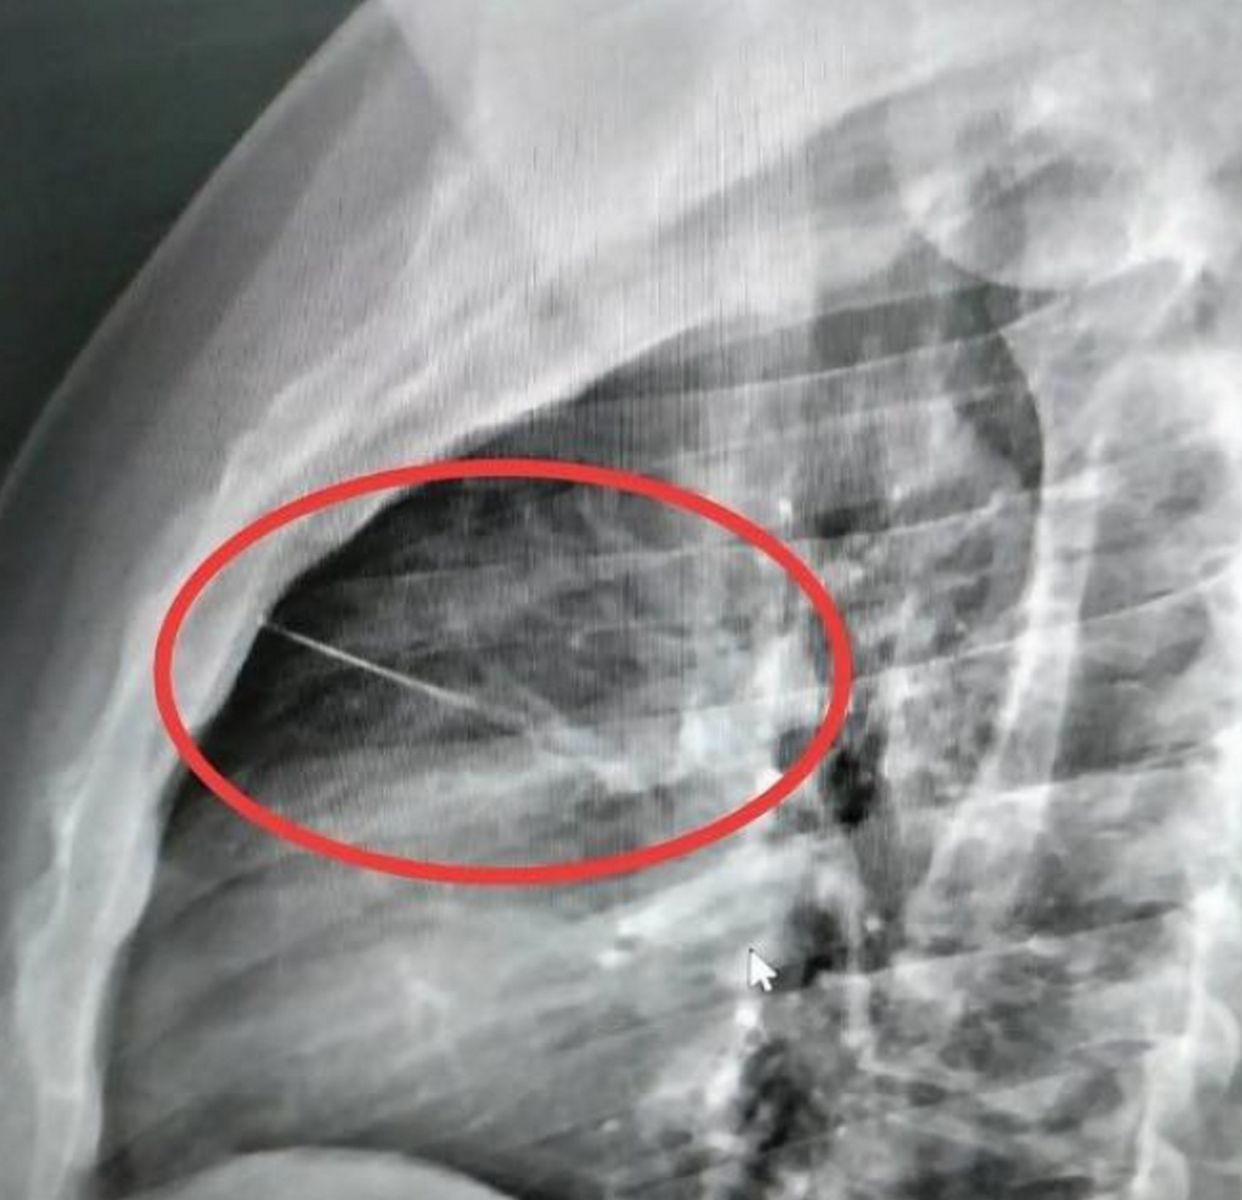

เมื่อไปถึงโรงพยาบาลอาการ ก็ยังไม่ดีขึ้นหมอจึงนำตัวไปเอ็กซ์เรย์ ปรากฏว่ามีวัตถุคล้ายของมีคมขนาดเล็กความยาวประมาณ 7 ซม.ทราบต่อมาว่าเป็นเข็มเย็บผ้า ฝังอยู่บริเวณหน้าอกซ้ายใกล้กับหัวใจ แพทย์จึงส่งตัวไปผ่าตัดที่โรงพยาบาลศูนย์บุรีรัมย์ เพราะเป็นจุดอันตราย

ขณะที่หลานคนเจ็บเล่าว่า ตอนนี้แพทย์แจ้งว่าอาการสาหัสจะต้องทำการผ่าตัด เบื้องต้นพบว่าเป็นเข็มเย็บผ้าที่น้าชายลืมไว้เองบนที่นอนและคาดว่าจะเหนื่อยจากการทำงานแล้วล้มตัวนอนบนที่นอนแล้วไปโดนเข็มแทงหน้าอกดังกล่าว